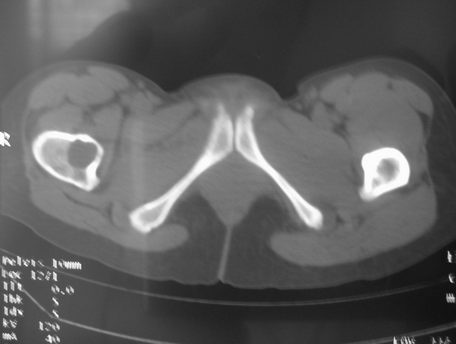

右股骨骨巨细胞瘤

女,31岁,右髋部疼痛半年,加剧两天不能行走

hhcckk发言:右股骨颈囊状骨质破坏,骨皮质变薄,周围硬化边不明显

dyqct发言:支持右股骨头、颈骨巨细胞瘤可能性大(跨越骺线).